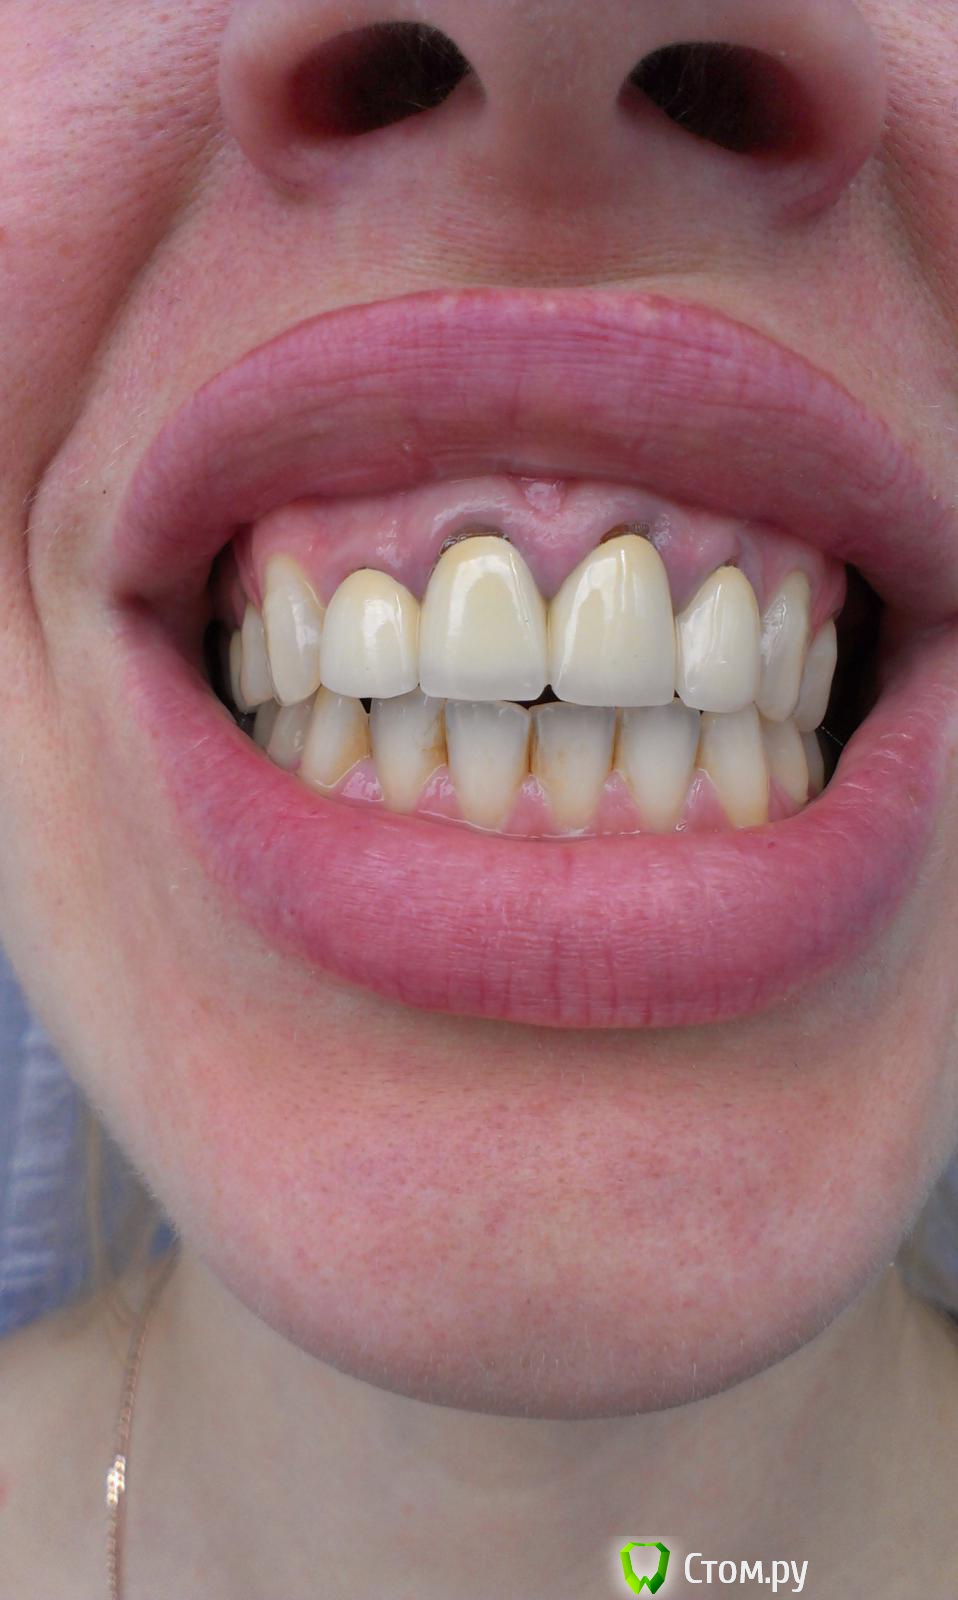

Ольга97-99 Опубликовано 6 сентября, 2014 Поделиться Опубликовано 6 сентября, 2014 Добрый день, уважаемые стоматологи. Прошу помощи... Ситуация с зубами плачевная... Не буду долго расписывать о том, как с 10 лет я не вылезаю из кресла стоматолога. Леченые зубки в небольном городе Н. Постоянно выпадающие пломбы, приводящие к повторному лечению. Депульпированны практически все. Периодичность посещения стоматолога - 3 мес., + манипуляции парадонтолога. Но к 26 годам имеем нижепредставленное.. С задними зубами все более или менее ясно - еще несколько на удаление, затем имплантация. С передними верхними... МК коронкам 7лет. Не беспокоят, боли, дискомфорта нет. Но эстетика оставляет желать лучшего. Еще, как говориться, не везет так не везет - улыбка десневая. И поднявшаяся синюшная десна во всю сияет. Было решено - настало время перемен. Мой обход ортопедов в нашем славном городе начался с мыслью вдохновляющей "заменить мк на дц". Более натуральный вид, к тому же рецессия десны должна была остановиться, так Интернет и доктора говорили )). Что имеем сейчас, мнения двух (на мой взгляд самых адекватных спецов) ортопедов: Первый: снимаем коронки, смотрим состояние корней. Если все нормально, штифты не трогаем, меняем пломбы и делаем дц. Но 80-90% вероятность, что корни испортились, либо будут повреждены (при снятии коронки выйдет штифт, разрушив корень). Тогда удаление, затем имплантация. Не буду портить мнение о себе и писать, что я испытывала после такого вердикта.... Второй: (его, кстати, посоветовал 1й) глянул (бегло) на мой снимки, говорит: снимаем коронки, вынимаем штифт, лечим каналы, делаем вкладки из дц, делаем коронки из дц. На мой вопрос "а если корень поврежден? или еще что-то не так пойдет" был ответ "зачем тебе это все знать, я доктор и я говорю тебе - будут коронки нормальные". Думаю, не стоит уточнять, что гарантий по сроку службы новых коронок я не услышала. Ну верней, прозвучала классика про кирпич на голову. Понятно, какой вариант мне запал в душу, и чего я бы хотела.. Но я могу хотеть одного, а реальность может быть совсем другой.. Не имею право на неоправданный риск, это же передние зубы... Пожалуйста, посмотрите снимки. Можно услышать Ваше мнение насчет возможности замены протезов передних верхних зубов. Заранее спасибо!!! Ссылка на комментарий